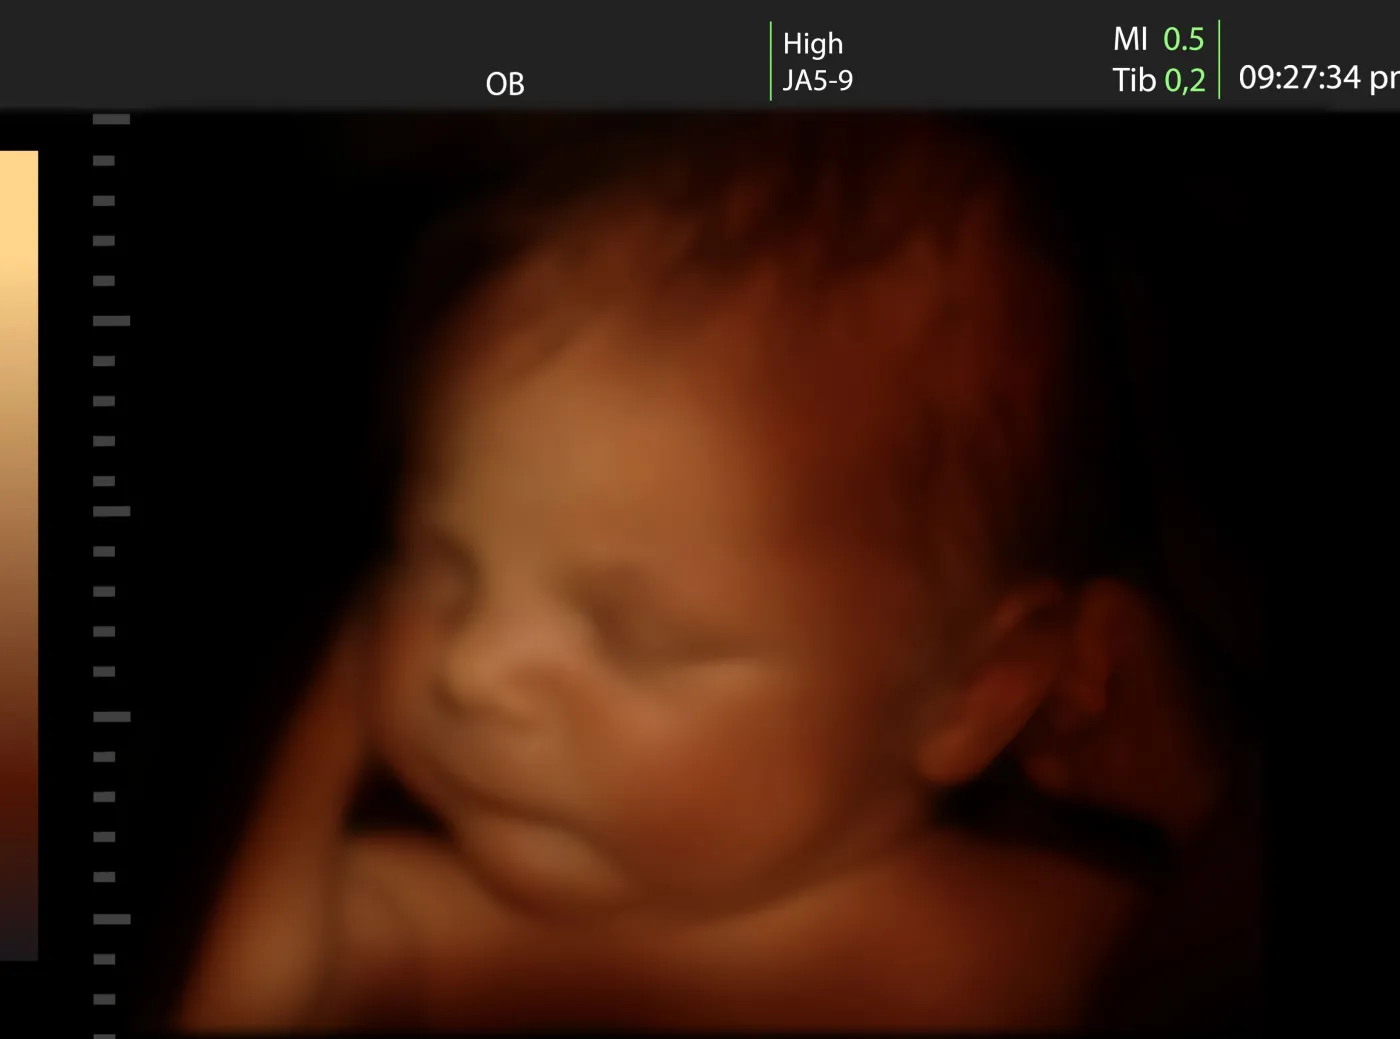

Nieinwazyjne badania prenatalne. Dlaczego warto je zrobić?

Myśl, aby dziecko urodziło się zdrowe, towarzyszy każdej kobiecie od początku ciąży.Obecnie, można to sprawdzić, zanim jeszcze maleństwo przyjdzie na świat. Nowoczesne technologie pozwalają na wykrycie ryzyka wystąpienia chorób, a co najważniejsze, są nieinwazyjne, czyli bezpieczne zarówno dla matki i płodu. Oto kilka najważniejszych, którym powinna poddać się ciężarna.